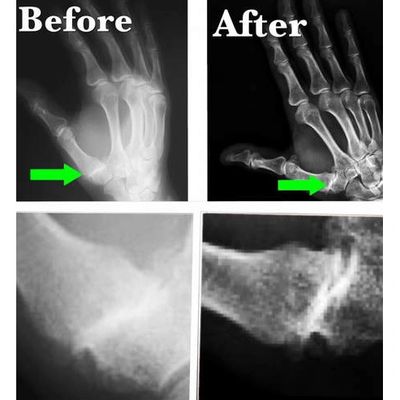

In a mishap, Tabitha inadvertently stabbed her left hand with a knife 18 years ago. The injury damaged her left ligament of her thumb. That straightforward movement, which we take for granted, actually caused pain and discomfort for almost 20 years. She had seen doctor after doctor with little improvement. They informed her that she would simply have to put up with it. This video is of her first treatment of SoftWave Li-ESWT.

1 treatment combined with a little physiotherapy, chiropractic adjustment & 4 minutes with the SoftWave LI-ESWT machine.